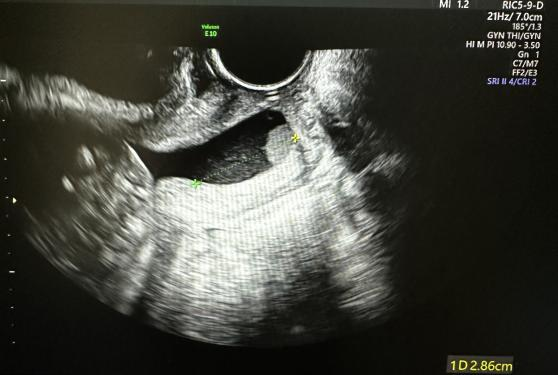

术后有效宫颈长约2.9cm

术后有效宫颈长度2.6cm